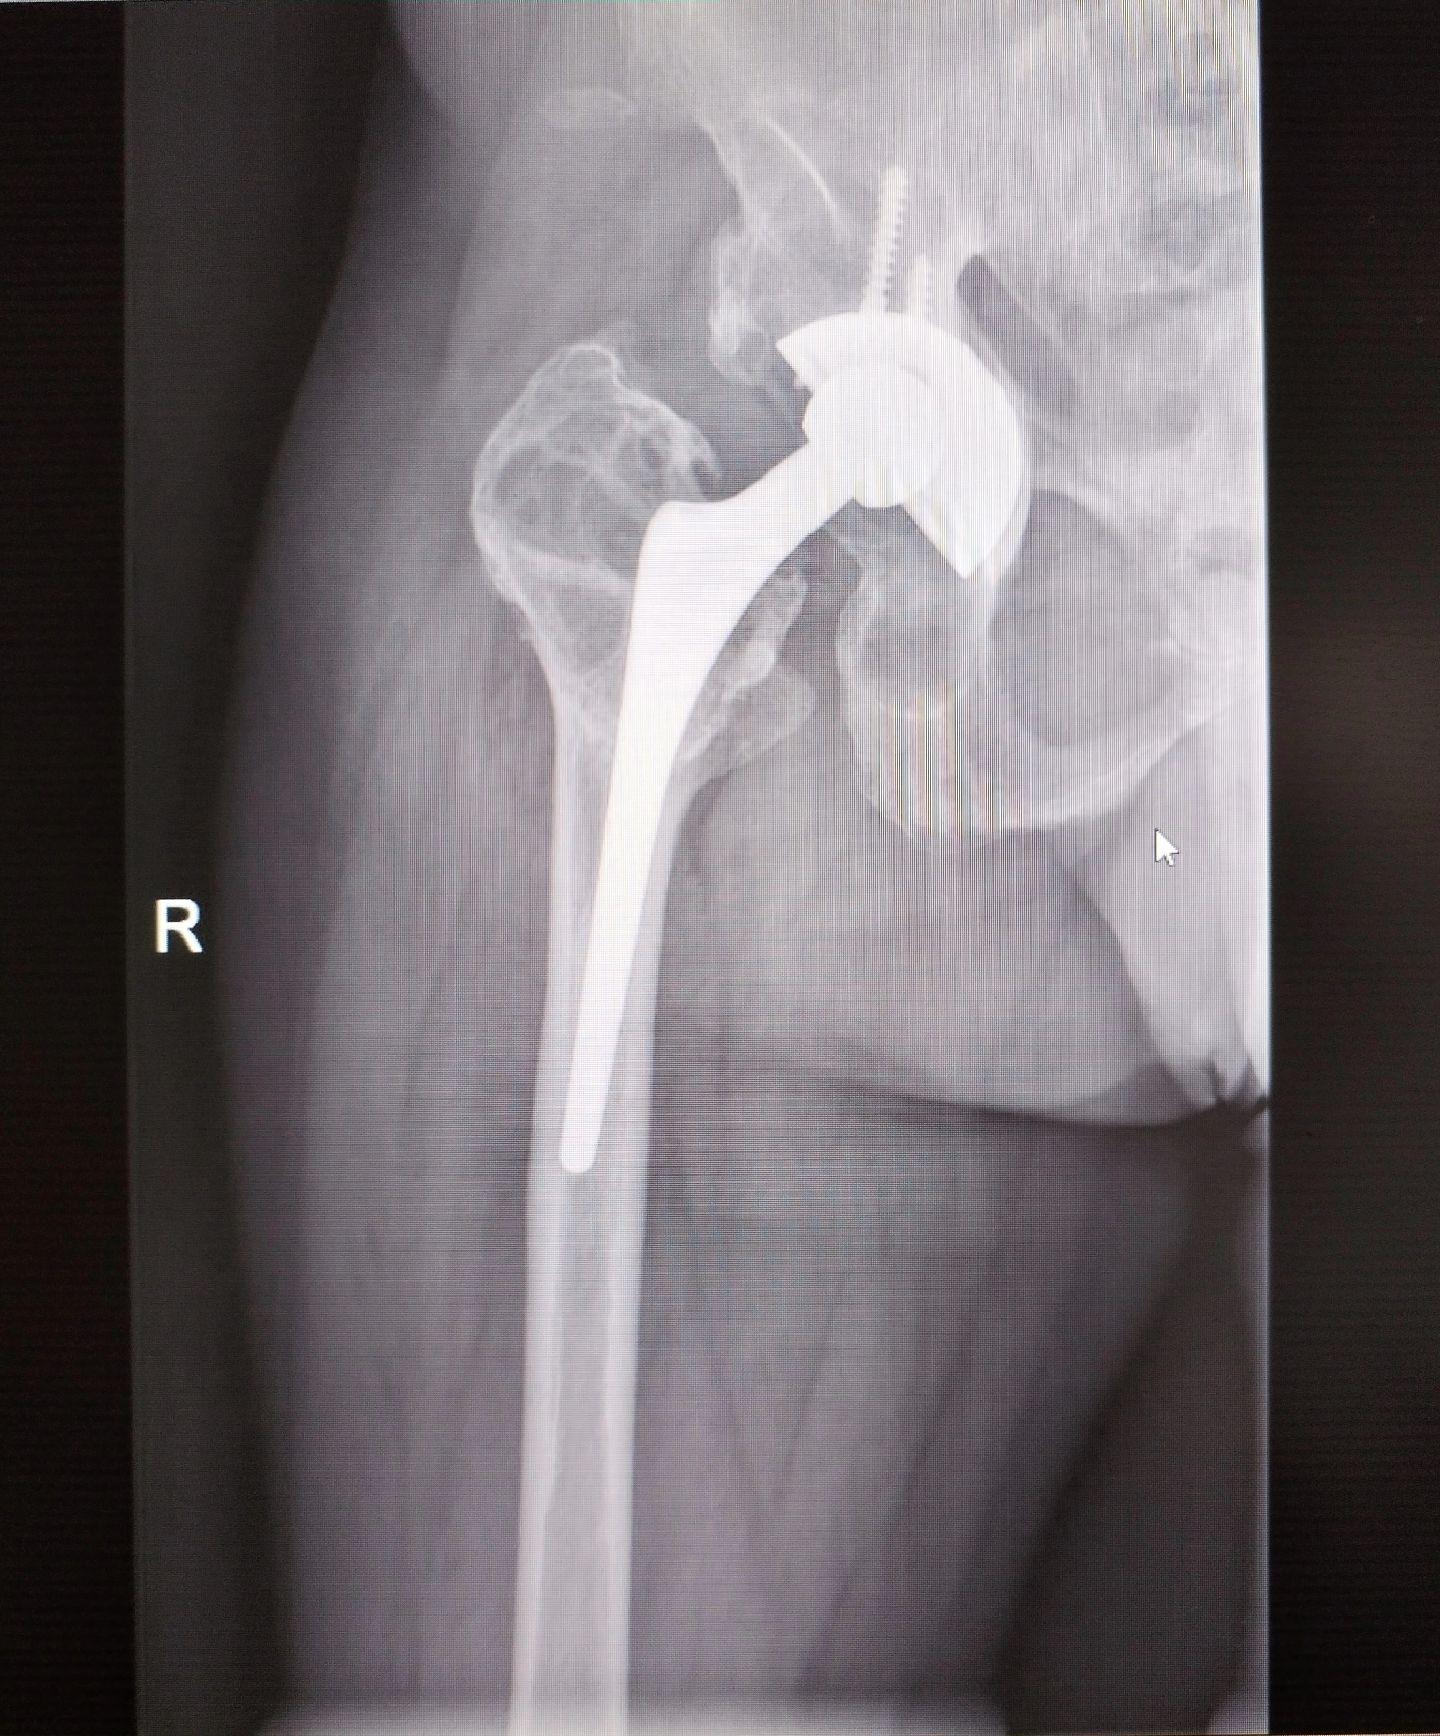

髋关节翻修术。髋关节置换术后假体磨损松动,双侧分次翻修。